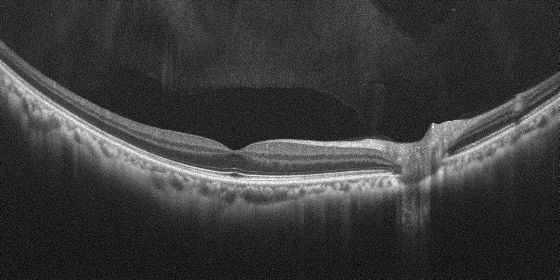

⚫“OCT-R1”は、OCT断層像とカラー眼底写真を一度のワンタッチ操作で撮影が可能。OCTにおいては従来機種上回るスキャン幅約14.7mm、深さ約13.4mm の広画角撮影を実現。広範囲を一度の撮影で高精細に画像化できるため、病変の早期発見などに貢献。

⚫高画質なOCT の断層像により、脈絡膜から網膜、硝子体の状態を観察することが可能。眼科系疾患の診断・治療方針の決定などに貢献。